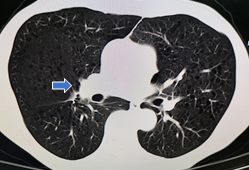

▲右肺下叶斜裂旁磨玻璃影,边缘毛糙,局部胸膜凹陷